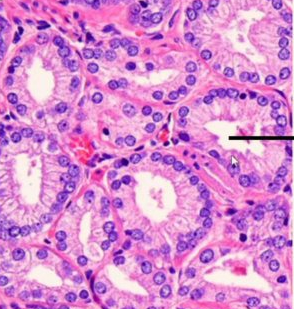

What Gleason Grade?

Grade 3